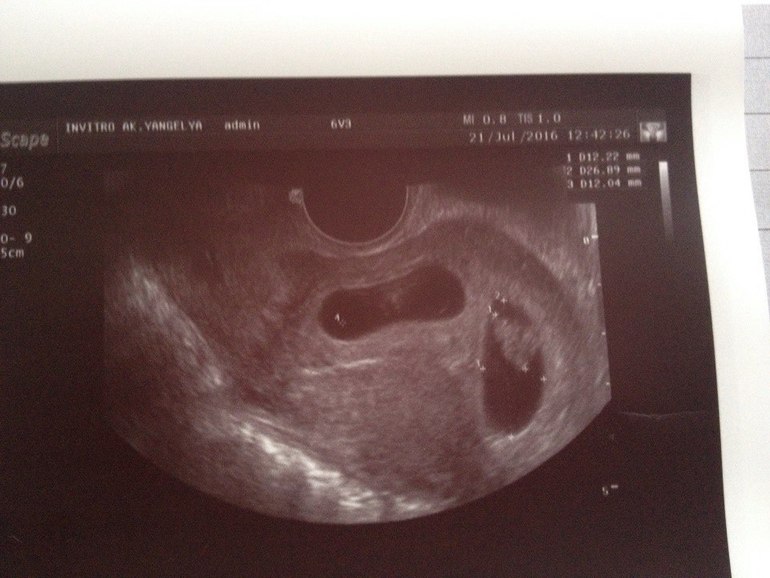

Результаты: УЗИ, КТГ, доплера, скринингаох, девочки....не ожидала я, конечно, таких новостей, но уже никуда не денешься) на 8 неделе сегодня УЗИ обнаружили два живых эмбриона в двух разных ПЯ, то есть по факту получилось что одновременно оплодотворилось две яйцеклетки (как такое вообще возможно????)....хотя на первом УЗИ было одно... Один по середине как положено, второй сильно сбоку (но Узист сказал, что это не страшно, главное, что он в полости матки). Забился в угол, скромняга, но по размеру они оба соответствуют срокам, сердцебиение есть у обоих...и я в шоке....Помогите переварить эту новость, дважды мамочки с двойняшками, поделитесь опытом первых недель!!!!